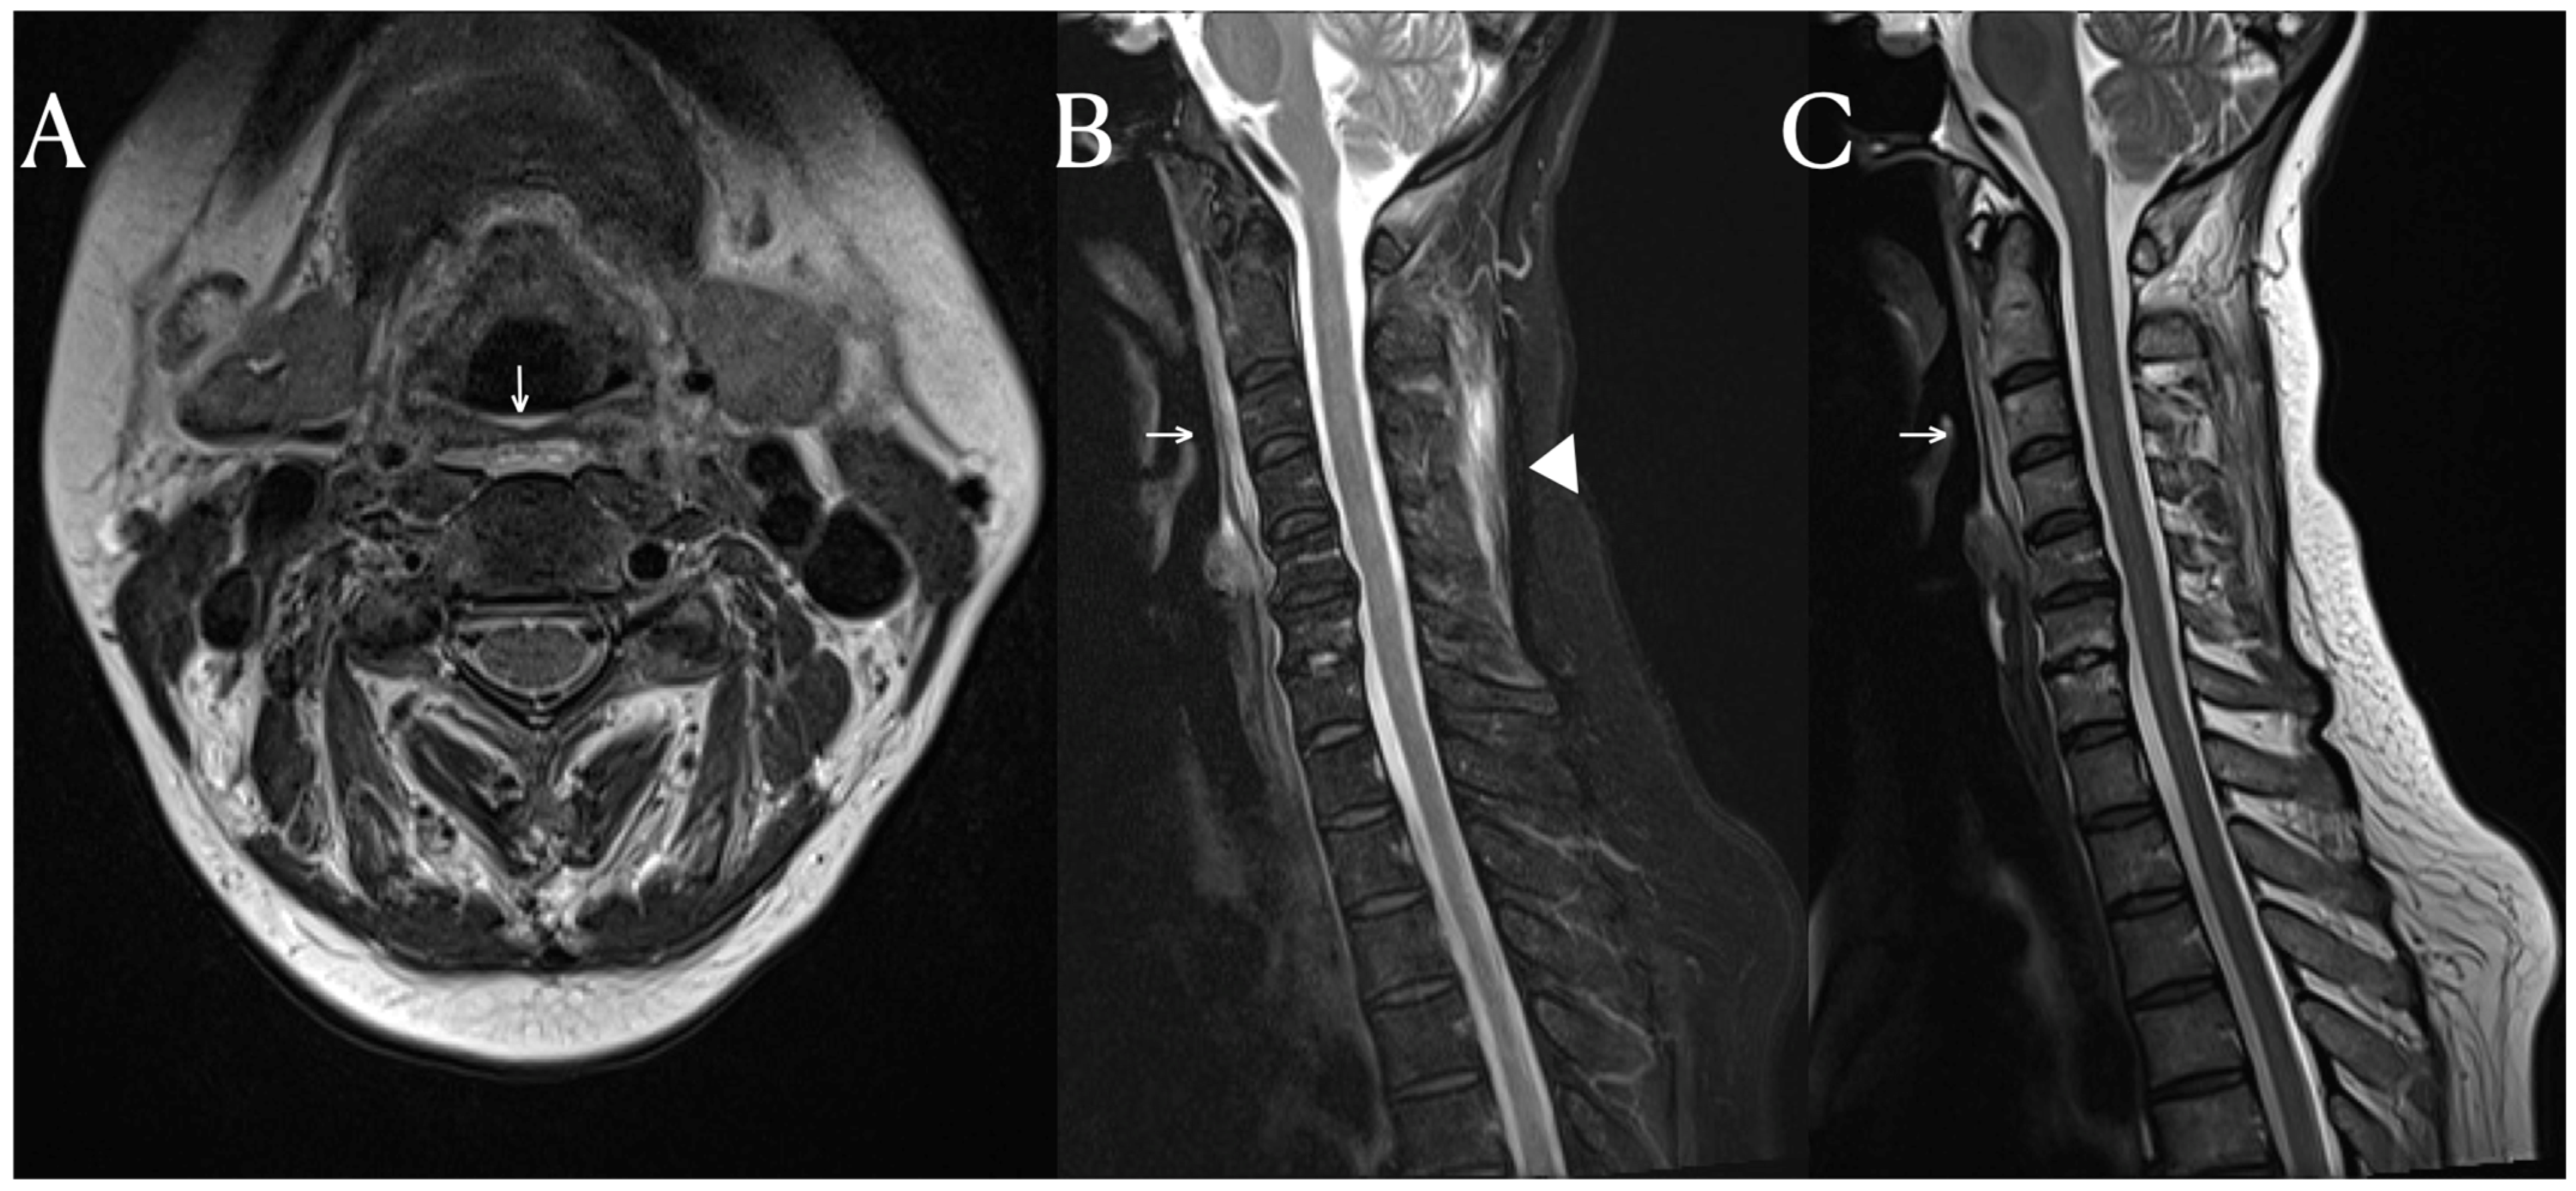

Although the PET-CT scan in this patient showed no evidence of FDG uptake in the prevertebral area and posterior neck fascia, it did reveal FDG uptake around multiple joints. (Figure 2) This suggests that this patient had systemic inflammation, which provides a possible explanation for the MRI signal changes. The fascia is a large complex of connective tissue found throughout the body. It contains nociceptors, meaning that inflammatory processes can lead to localized pain [6]. Additionally, many nerves traverse through the fascia to reach their respective locations; so, inflammation-induced changes in the extracellular matrix (ECM) can increase fascial stiffness [7]. These alterations can influence fascial nociception and stimulate nerves through stiffness, potentially causing musculoskeletal pains. So, hydrodilation procedures are performed to release peripheral nerve compression caused by stiff fascia [8]. The deep cervical fascia, palmar fascia, iliotibial band, and thoracolumbar fascia are known fasciae considered as potential causes of musculoskeletal pain [9]. While research on neck fascia is limited compared to other areas, previous study have shown increased fascia thickness in the SCM (sternocleidomastoid) and middle scalene muscles in patients with chronic neck pain [10]. Additionally, fascial manipulation reduced fascia thickness and pain.

Figure 2. FDG PET-CT finding. Bilateral shoulder shows uneven FDG uptake (D). Both wrists, hips, and knees show increased FDG uptake (A). However, in the FDG PET-CT images of the C3 (B) and C5 spinal level (C), there is no hot uptake in the prevertebral soft tissue and posterior neck fascia areas, where signal changes were seen in the MRI.